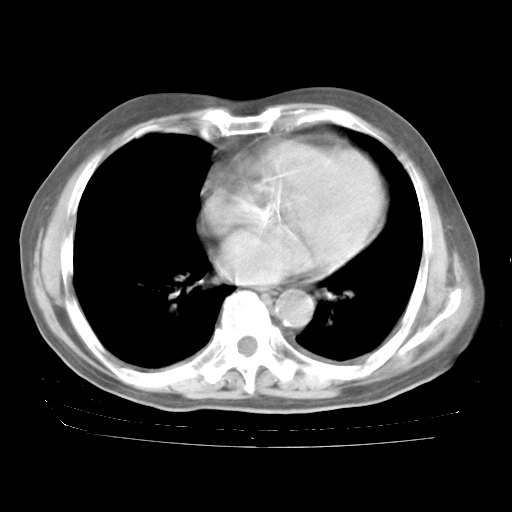

4月28日肺部CT——再次出现类似去年5月9日——透光度降低,“间质性”改变。

4月28日肺部CT——再次出现类似去年5月9日——磨玻璃样、间有“粟粒样”改变。

4月28日肺部CT